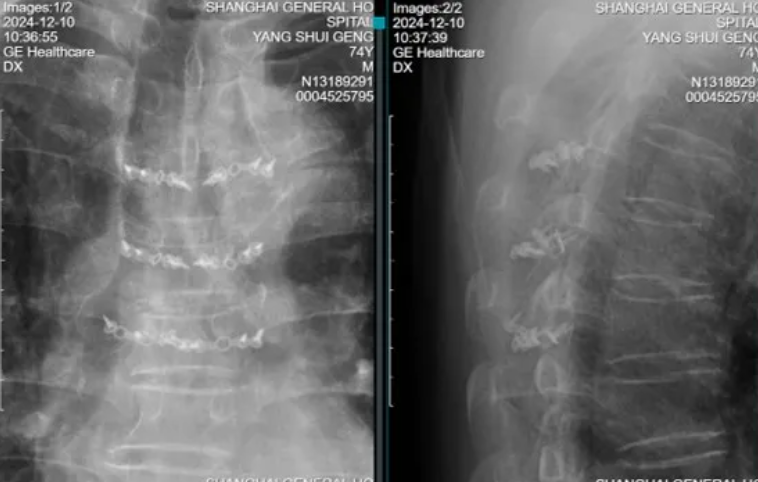

术后3天引流50ml以下拔除引流管,术后复查X线:

T4-6椎板回植术后,椎板、棘突序列正常